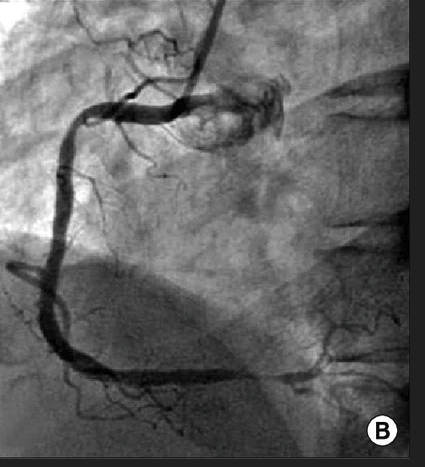

(B) The proximal and distal spasms of the right coronary artery are improved by repeated intracoronary injection of nitroglycerine.